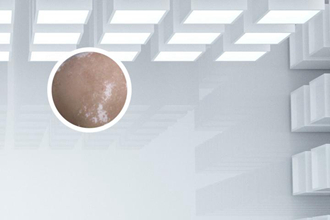

308激光治療白癜風(fēng)的效果因人而異,一般需要經(jīng)過(guò)一個(gè)療程(10次左右)才能看到顯然效果,通常在1-3個(gè)月內(nèi)可以恢復(fù)正常膚色。但具體停止時(shí)間需根據(jù)患者個(gè)體情況而定,部分患者可能需要更長(zhǎng)時(shí)間的治療。

當(dāng)白斑顏色基本恢復(fù)正常時(shí),可以停止烏魯木齊308激光治療。具體停止時(shí)間建議咨詢專業(yè)醫(yī)生,根據(jù)皮膚恢復(fù)情況進(jìn)行判斷。